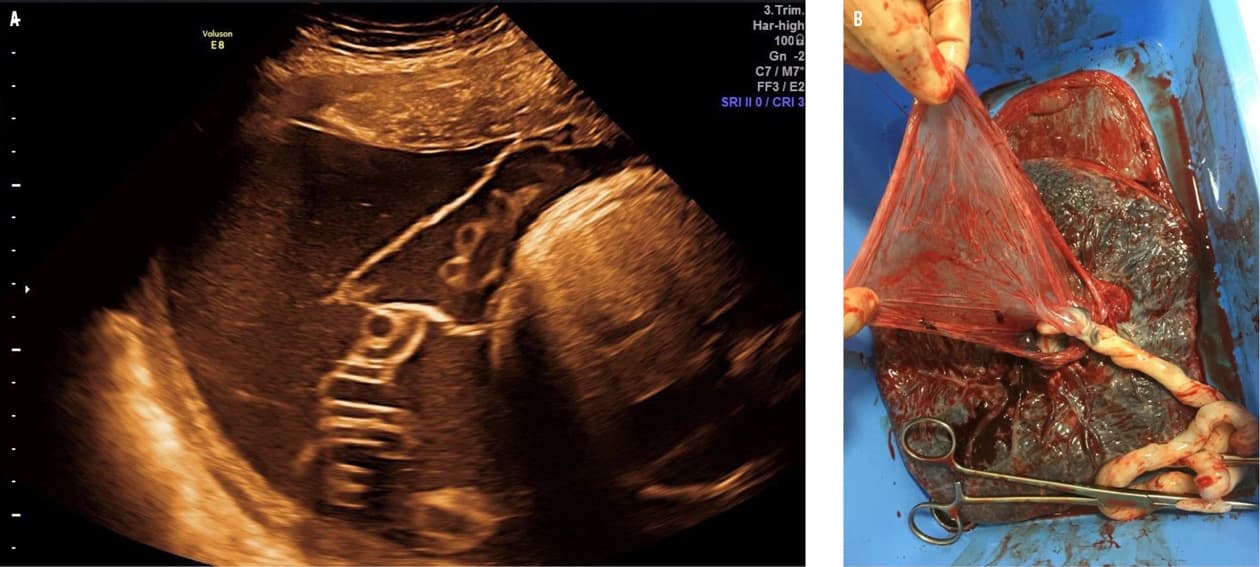

En flergangsgravid, 34-årig kvinde fik graviditetsbetinget diabetes mellitus og polyhydramnios. Ved gestationsalder 36 uger + 1 dag skubbede hendes fireårige barn hende hårdt i maven i forbindelse med leg, hvorved hun mærkede »et smæld« i højre side og efterfølgende en anderledes fornemmelse af liv. Hun blev samme dag undersøgt af en jordemoder, hvor alt blev fundet normalt. Tre dage senere henvendte hun sig igen med fortsat fornemmelse af »mindre liv«. Der blev foretaget en ultralydskanning, hvor man fandt et foster med normal vækst og flow samt en stor chorion-amnion-separation (CAS) i højre side (A). Der blev foretaget subakut sectio og forløst en lille, men rask pige.

CAS opstår, når amnionhinden helt eller delvist adskilles fra chorionhinden og kun er sammenhængende ved navlesnorens vedhæftning til placenta [1]. Hinderne fusionerer omkring uge 16, og herefter betragtes CAS som patologisk. CAS kan opstå iatrogent eller spontant og er associeret med for tidlig fødsel og for tidlig vandafgang [2]. CAS er også associeret med intrauterin død, da der menes at være en risiko for, at de løse hinder kan danne et bånd rundt om navlesnoren med risiko for kompression [3], hvilket illustreres tydeligt på B.